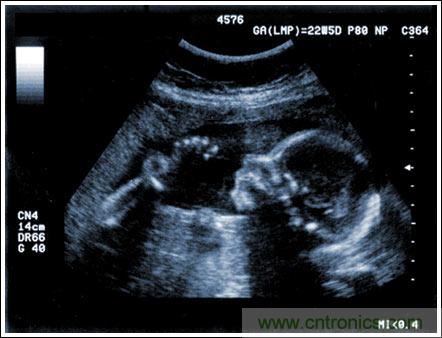

【導讀】該應用筆記介紹了超聲成像系統的設計考慮,討論成像系統的小型化、低成本和便攜化的發展趨勢,同時闡述了在小型系統中實現大型車載系統所具備的性能和診斷能力的重要條件。文章探討了超聲系統的子功能以及對電子元件的要求,重點討論了傳感器、高壓復用器、高壓發射機、成像通道接收機、數字波束成形、波束成形數字信號處理及顯示處理等。

通過發射超聲能量進入人體,接收并處理返回的反射信號,相控陣超聲系統可以生成體內器官和結構的圖像,映射血液流動和組織運動,同時提供高準確度的血流速度信息。傳統設計中,構建這樣的成像系統需要大量的高性能相控陣發射器和接收器,使得車載設備體積龐大且價格昂貴。近年來,隨著集成工藝的進步,設計人員能夠獲得小尺寸、低成本而且高度便攜的成像系統方案,并可達到接近大型成像設備的性能指標。而新的設計挑戰依然存在,即在進一步提高方案集成度的同時提高系統性能和診斷能力。